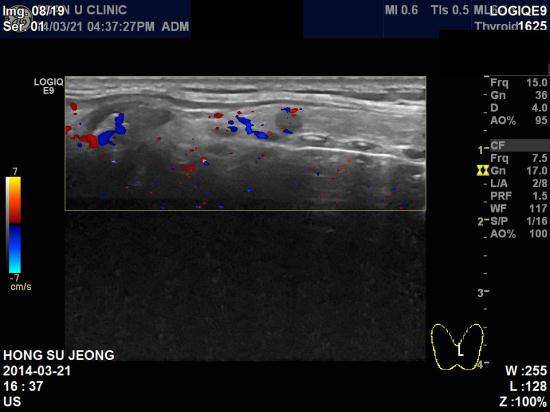

아산유외과 개원 후 21번째 갑상선암 진단.

피곤한증상이 오래전부터 지속되어 내원하신 54세 남성분이십니다.

피곤한 증상이 있으면 갑상선질환을 의심해 볼 수 있기에

본원에서 갑상선 초음파를 시행하였습니다.

초음파상 갑상선 협부에 0.47 cm 의 결절이 발견되었고

양성의 혹과는 보여지는 양상이 달라 세포검사 시행결과

갑상선 유두암으로 진단되었습니다.

최근 남성의 갑상선암도 증가하고 있기때문에 주의가 필요합니다.